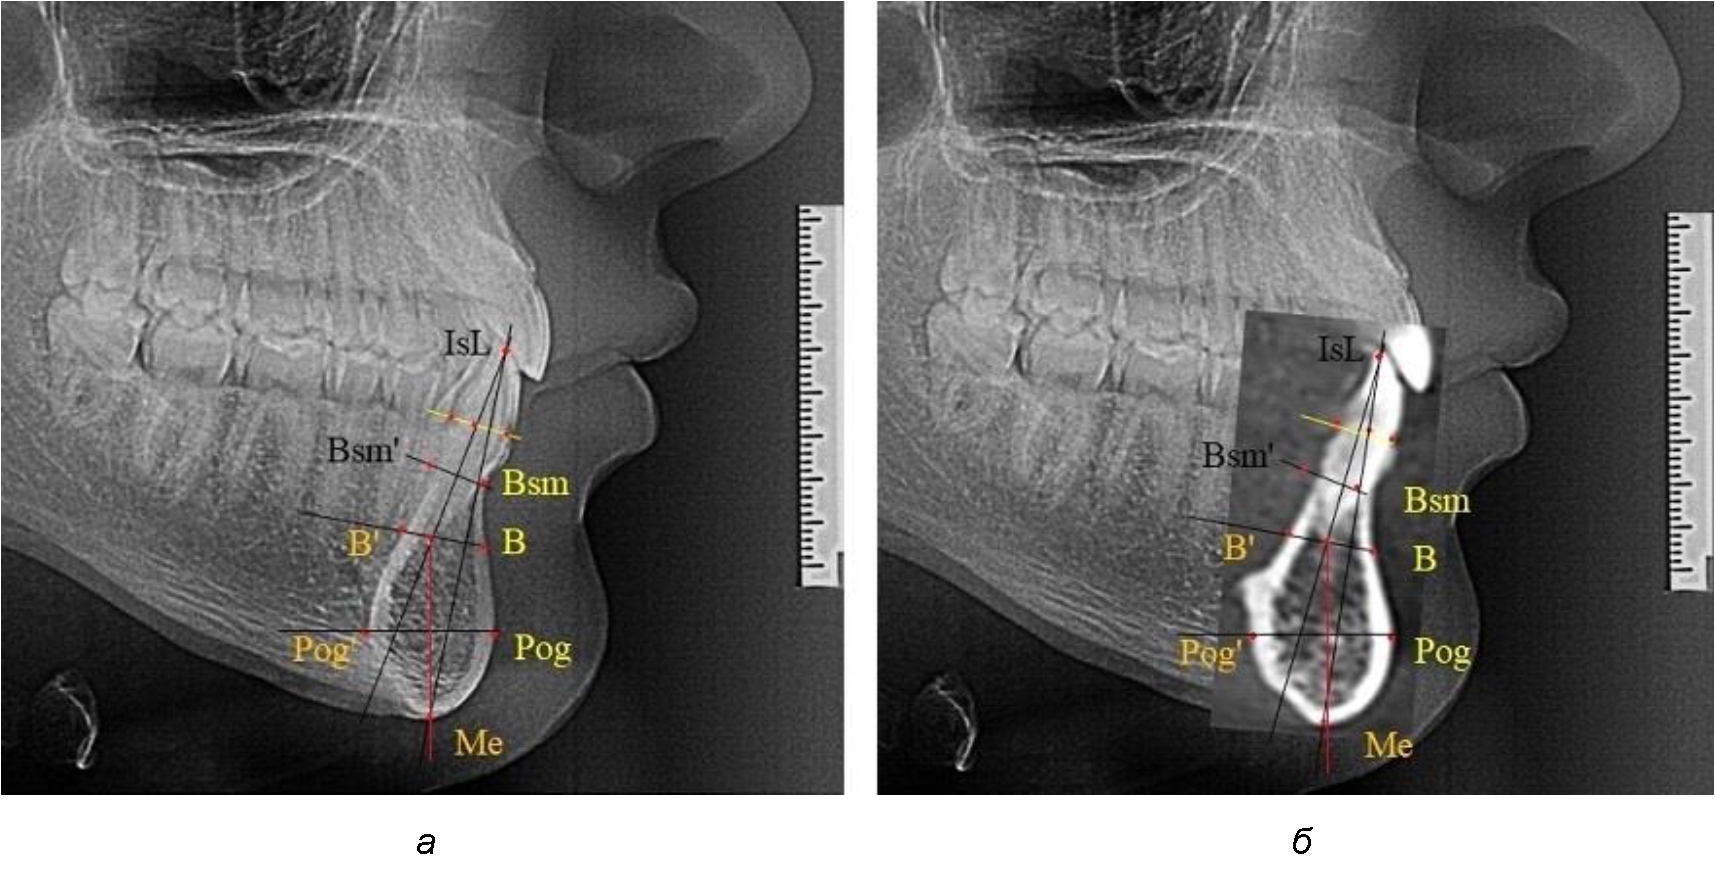

Нередко отмечается деформация подбородочного выступа и различное его положение по отношению к зубоальвеолярной части сегмента. При мезиальной окклюзии нередко нижняя подбородочная точка смещается кзади по отношению к условной срединной вертикали нижнего резца, а при дистальной окклюзии отмечается компенсаторное отклонение подбородка кпереди (рис. 5).

Рис. 5. Особенности нижнечелюстного резцового сегмента на ТРГ у людей при мезиальной (а) и дистальной (б) окклюзии

Кроме того, так же как и у людей с физиологической окклюзией, определялось различие в положении апикальных точек Downs и Schwarz, что, по нашему мнению, может определять тактику лечения патологических форм протрузии/ретрузии резцов с учетом биотипа костной ткани.